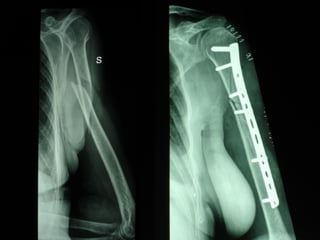

Dal Gennaio 2000 al Febbraio 2006 abbiamo trattato 167 fratture chiuse  con placca percutanea  in 164 pazienti :  27 lesioni diafisarie di gamba, 12 piloni tibiali ,  11 fratture prossimali di tibia, 36 fratture sovracondiloidee di femore, 17 fratture diafisarie di femore, 43 fratture metaepifisarie prossimali di omero, 21 diafisarie d’omero.  156 guarigioni 8 fallimenti

I buoni risultati ottenuti dipendono da 5 punti fondamentali:   una accurata riduzione percutanea della frattura  precise vie di accesso  l’utilizzo della placca che consenta il più lungo braccio di leva possibile il pretensionamento della placca  una sintesi con un ridotto numero di viti

Precise vie di accesso

Placche lunghe e pretensionate

Placche lunghe e pretensionate Sintesi con un ridotto numero di viti